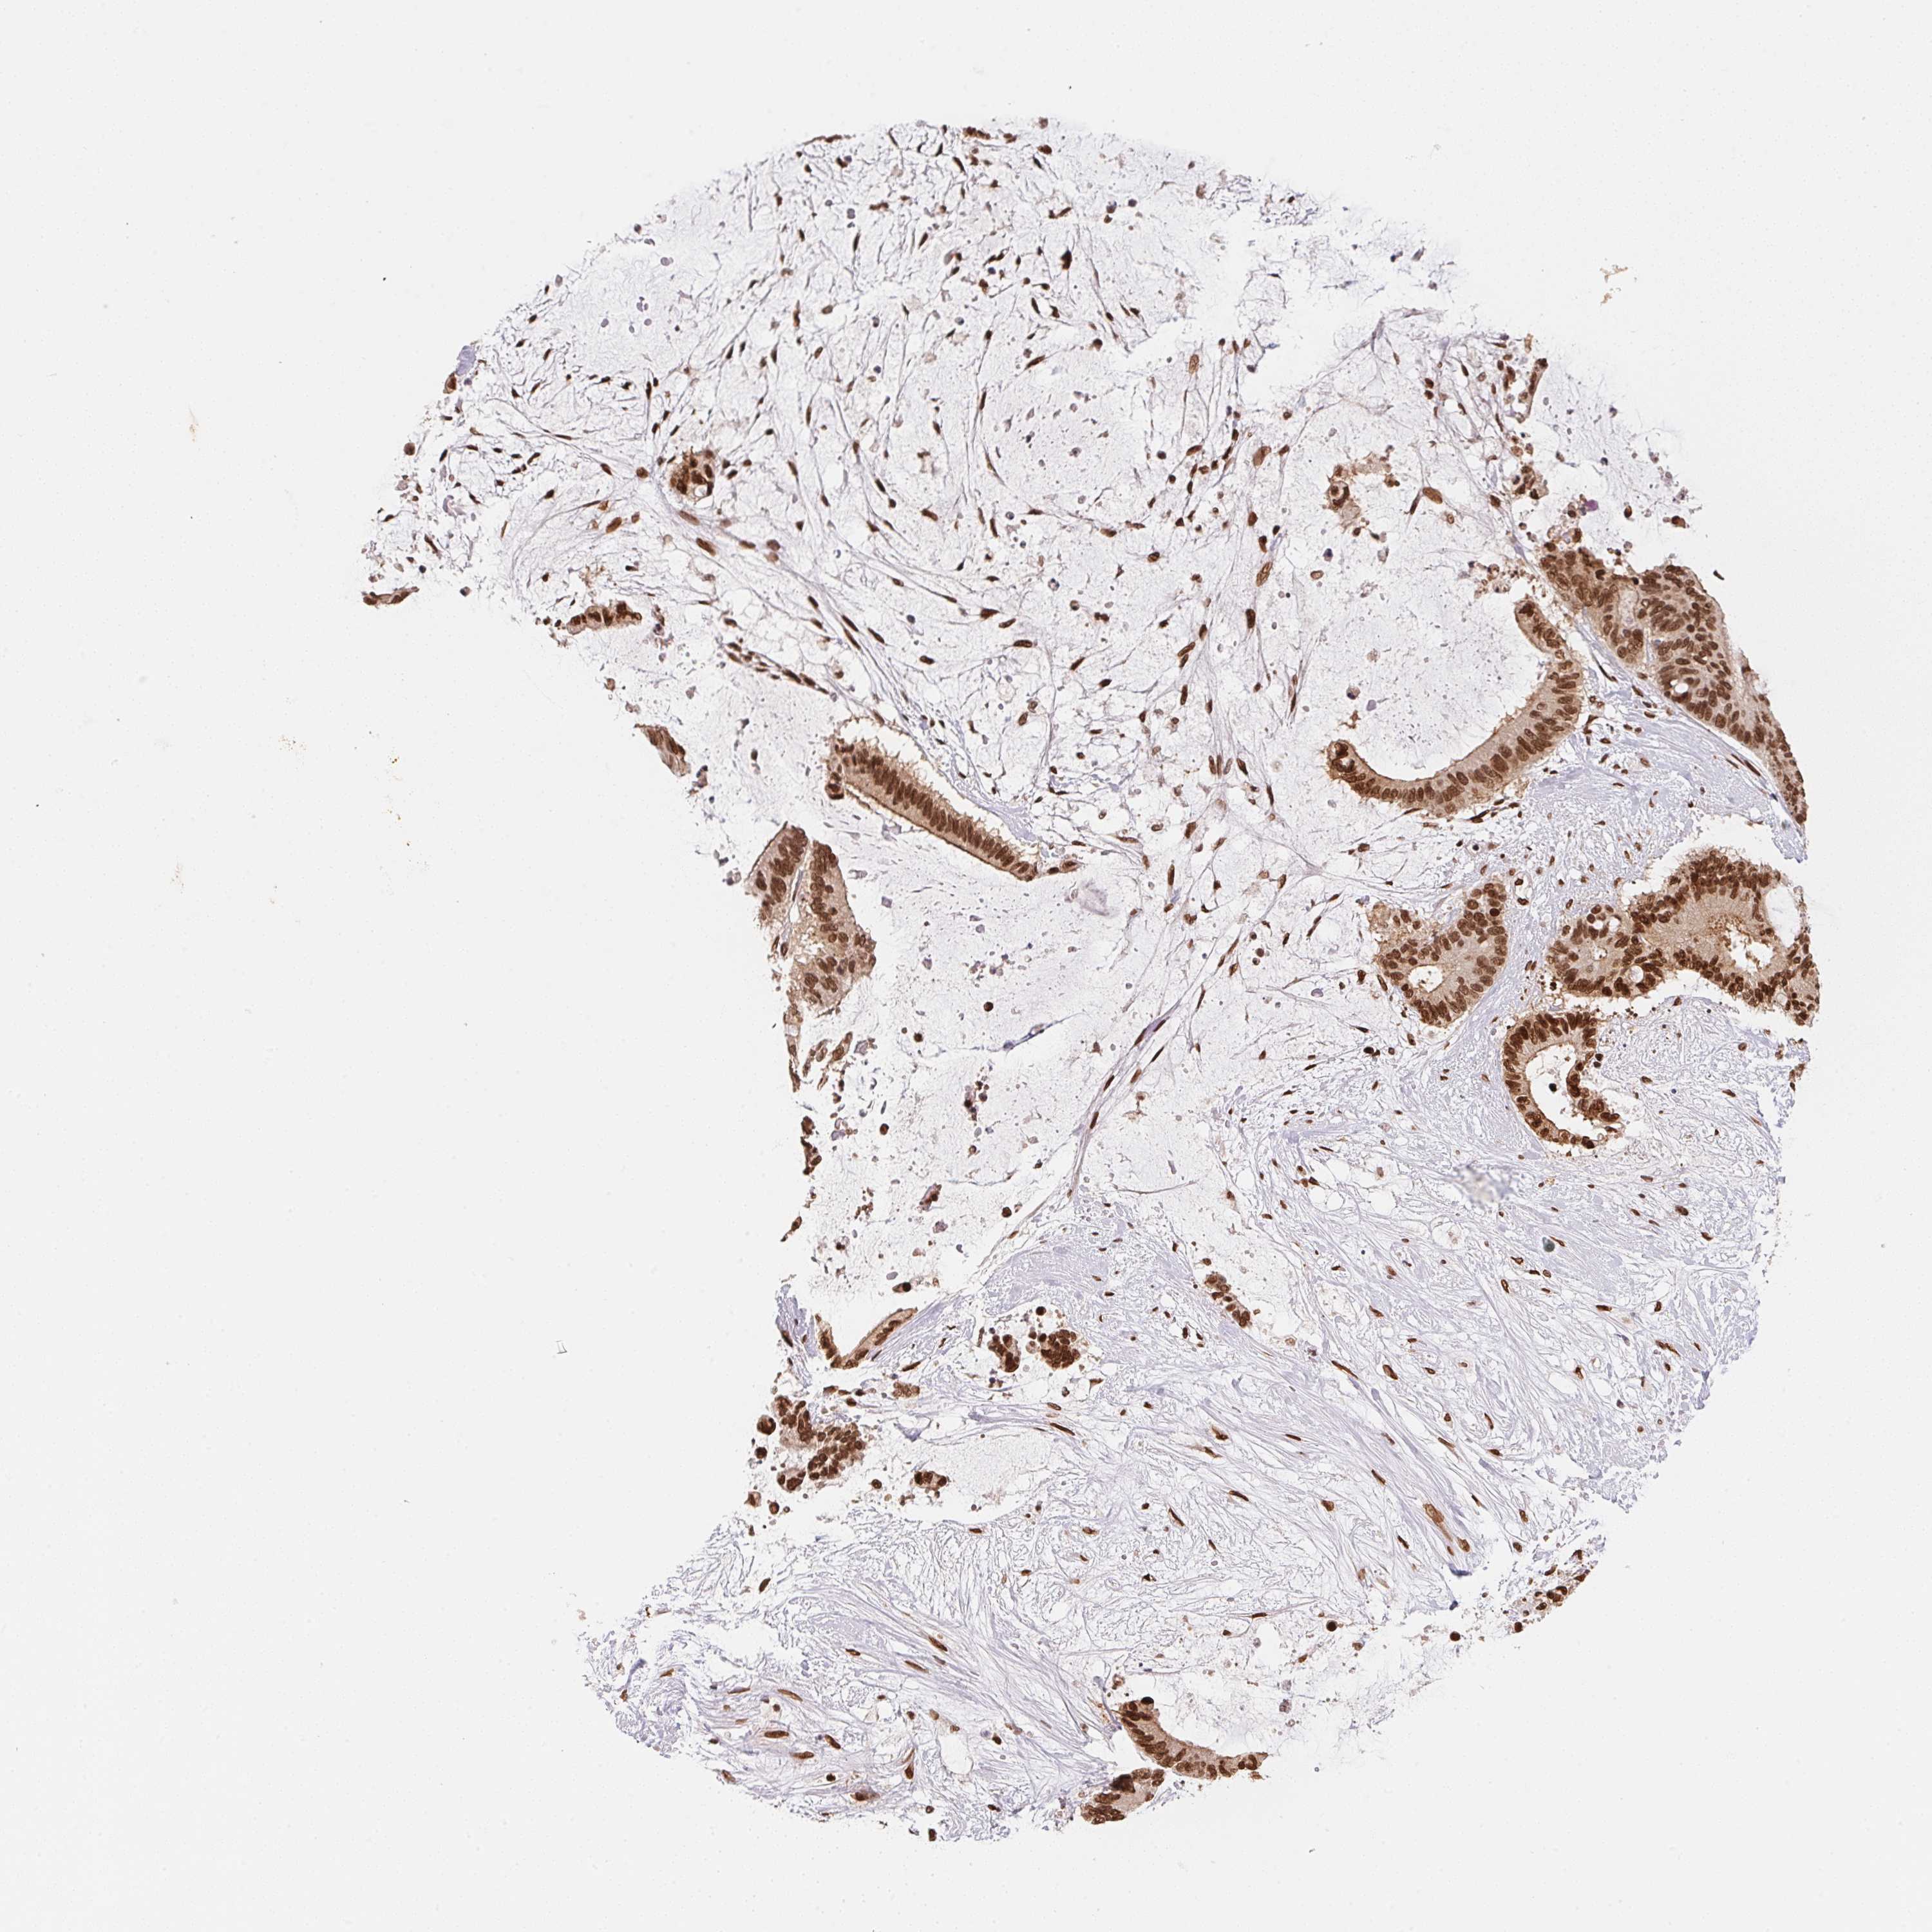

LIVER CANCER - Protein expressioni

A mouse-over function shows sample information and annotation data. Click on an image to view it in a full screen mode. Samples can be filtered based on level of antibody staining by selecting one or several of the following categories: high, medium, low and not detected. The assay and annotation is described here.

Note that samples used for immunohistochemistry by the Human Protein Atlas do not correspond to samples in the TCGA dataset.

Antibody stainingi

Antibody staining in the annotated cell types in the current human tissue is reported as not detected, low, medium, or high, based on conventional immunohistochemistry profiling in selected tissues. This score is based on the combination of the staining intensity and fraction of stained cells.

Each image is clickable and will lead to virtual microscopy that enables deeper exploration of all samples and also displays staining intensity scores, fraction scores and subcellular localization as well as patient and tissue information for each sample.

Antibody HPA052943

Staining

High

Medium

Low

Not detected

Intensity

Strong

Moderate

Weak

Negative

Quantity

>75%

75%-25%

<25%

None

Location

Nuclear

Cytoplasmic/membranous

Cytoplasmic/membranous,nuclear

Carcinoma, Hepatocellular, NOS

Cholangiocarcinoma